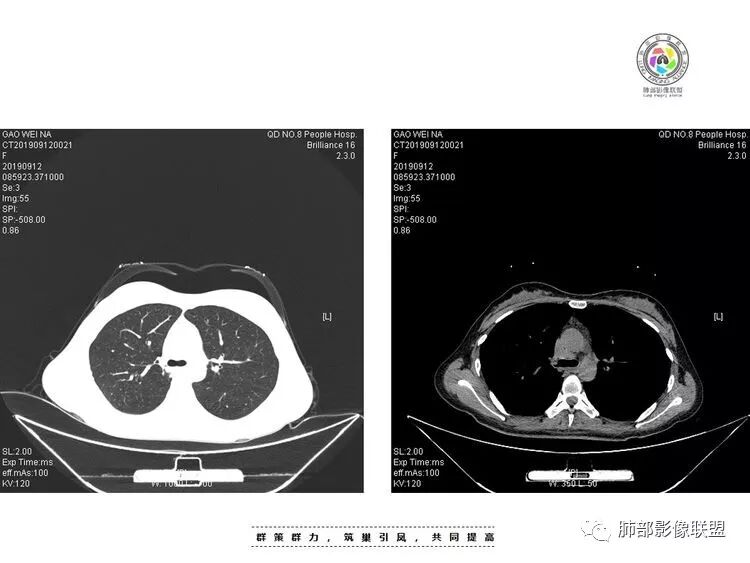

29岁女性,既往体健。咳嗽咳痰(白黏痰)一月,加重一周(黄白痰),发热3天伴咯血。血常规:中性粒、CRP升高,血沉增高。CT:右肺下叶不规则厚壁空洞伴散在树芽、小叶中心结节。空洞内壁光滑,似见液平。无胸腔积液及明显纵膈肿大淋巴结。予左氧及美洛西林舒巴坦治疗12天,临床症状减轻。复查CT见空洞明显吸收缩小,增强见薄壁空洞,内有液平,引流支气管增厚。考虑感染;是单纯细菌感染还是结核感染?还是细菌合并结核?建议痰找抗酸杆菌,痰培养,并继续复查肺部CT,可完善支气管镜检查。

结核空洞相对薄壁且很少液平,如此明显洞内积液也会怀疑合并细菌等感染。

抗感染治疗后短期复查右肺病灶变化明显,部分病灶如空洞性病灶明显吸收,部分病灶稍有增大融合(如背段病灶)。